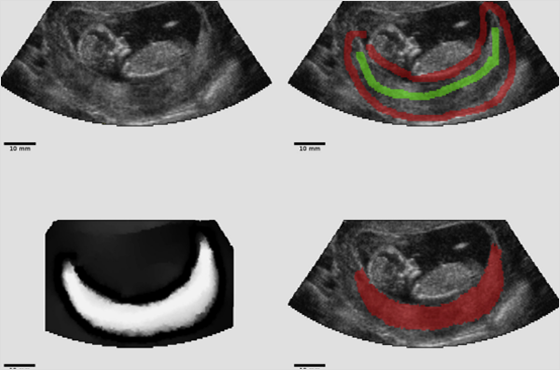

학회가 전하는 초음파 소식 Ultrasound in the Assessment of Obstetric hemorrhage and Postpartum Uterine Abnormalities 2026-02-02 부인과 수술에서 수술 중 초음파(IOUS)의 역할과 최신 임상 응용 2026-01-06 New insights into functional imaging of the placenta 2025-12-01 더보기